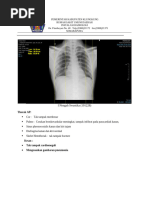

Thorax PA normal

Foto THORAX, PA view, posisi erect, asimetris, inspirasi dan kondisi cukup, hasil :

- Tampak corakan bronchovascular normal

- Tampak kedua sinus costofrenicus lancip

- Tampak kedua diafragma licin

- Cor, CTR < 0,5

- Sistema tulang yang tervisualisasi intact

Kesan :

- Pulmo tak tampak kelainan

- Besar Cor normal